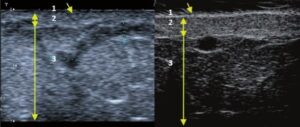

Die Doppler-Sonographie ermöglicht die Darstellung großer Gefäße und Perforatoren, die sich meist in tieferen Bereichen des subkutanen Gewebes befinden. Mit klassischem Ultraschall lassen sich kleinere Gefäße jedoch nicht darstellen. Für die Darstellung kleinerer Gefäße, die oberflächlich unter der Epidermis und im oberen subkutanen Gewebe liegen, wird HFU eingesetzt. Mit Sonden über 20 MHz Frequenz erhält man hochauflösende Ultraschallbilder, auf denen Objekte kleiner als 0,1 mm unterscheidbar sind. Mit zunehmender Auflösung nimmt jedoch die Eindringtiefe ab. Je nach Sonde und Gerät beträgt die maximale Eindringtiefe etwa 20–30 mm. Diese Eindringtiefe bei gleichzeitig hoher Bildauflösung ermöglicht die Beurteilung sehr kleiner Gefäße. HFU erlaubt die genaue Bestimmung des Verlaufs und der Lage kleiner Gefäße in der Haut, was entscheidend für die Wahl der Verschlussmethode und die Planung des Eingriffs ist. Oft sind an der Hautoberfläche nur wenige Gefäße sichtbar – erst durch die Ultraschalluntersuchung lässt sich die tatsächliche Anzahl und der Verlauf feststellen. Für einen erfolgreichen Verschluss muss das gesamte Gefäß behandelt werden, nicht nur der sichtbare Teil, da sonst eine schnelle Rekanalisation erfolgt (7). Häufig ändert das an der Haut sichtbare Gefäß seinen Verlauf, wird gewundener und zieht in tiefere Hautschichten (8). HFU ermöglicht zudem die Darstellung der Perforatoren zwischen kleinen Gefäßen und die Messung grundlegender Parameter wie Durchmesser, Wandstärke, Tiefe und Blutfluss (6). Mit der 40-MHz-Sonde von Ultrasonix kann auch der Blutfluss mittels Farbdoppler visualisiert werden.